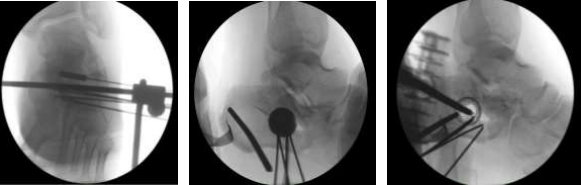

Reduction Technique

The minimally invasive fracture reduction employed a meticulous sequence of maneuvers to achieve optimal anatomical restoration. Initial reduction of the lateral and medial walls of the calcaneus was facilitated using pelvic reduction clamp over a soft tissue protection. This maneuver enabled us to reduce the blowout lateral wall which was evaluated by fluoroscopic guidance. Following lateral wall reduction, a single Steinmann pin was employed to maintain the alignment and act as a "joystick" for further adjustments. The pin was inserted medially and advanced laterally in the most posterior part of the calcaneus away from fracture to effectively restore the calcaneal length. A Steinmann pin holder provided additional control during this maneuver to prevent varus. To address the posterior facet depression, a small (approximately 1 cm) lateral stab incision was created. An AO periosteal elevator was then introduced through the fracture gap, ensuring minimal soft tissue disruption. This instrument facilitated mobilizing the fragments and elevation of the depressed posterior facet fragment, restoring its anatomical position. After elevation of the facet and reducing the crucial angle of Gissane, gap was created and before introducing the stent four Kirschner wires (K-wires) was strategically placed at the inferior part of the defect from medial to lateral in one row, the purpose was to introduce the stent above it and during inflation to direct the force only upward to reduce and hold the posterior facet in its anatomic position. An intraoperative X-ray confirmed the preliminary reduction and restoration of the crucial angle of Gissane closer to the normal range.

To further stabilize the fracture and maintain the restored articular congruity, the minimally invasive procedure incorporated the use of Vertebral Body Stenting System (VBS) from DePuy Synthes. Then 4 K-wires was introduced from lateral to medial at the inferior part of the created gap to prevent inferior displacement of the stent. Through the previously created lateral stab incision, a medium-sized Vertebral Body Stent with Balloon was introduced into the fracture void. This pre-inflated stent, with a maximum volume of 4.5 ml and maximum inflation pressure of 30 ATM, served as a crucial tool for both reduction and internal support. Inflation proceeded under fluoroscopic guidance, gradually increasing pressure until an appropriate resistance was encountered at around 20 ATM (Figure 7). The inflated stent acted as a highly effective reduction tool. Its expandable nature compacted the softer inner bone within the calcaneus, simultaneously creating a void space and elevating the depressed posterior facet fragment back to its anatomical position (Figures 9, 10, 11, and 12). This restoration of height and improved articular surface alignment contributed significantly to fracture stabilization were the inferiorly placed K-wires prevented downforce. Following successful VBS deployment, and stent visualization to be holding the reduction radiopaque, injectable polymethyl methacrylate cement (VERTECEM V+ CEMENT KIT) from DePuy Synthes was utilized as a void-filling agent. Under fluoroscopic control, 4 ml of cement (2 syringes) were injected into the newly created cavity within the calcaneus (Figure 8). This cemented augmentation provided additional stability and maintained the fracture reduction. After a ten-minute cement curing period, the temporary Kirschner wires were safely removed. The surgical site was meticulously closed, dressed, and supported with a below-knee backslab for additional immobilization. Final intraoperative radiographs confirmed satisfactory reduction, restoration of the crucial angle of Gissane, and appropriate cement distribution (Figures 13 and 14).